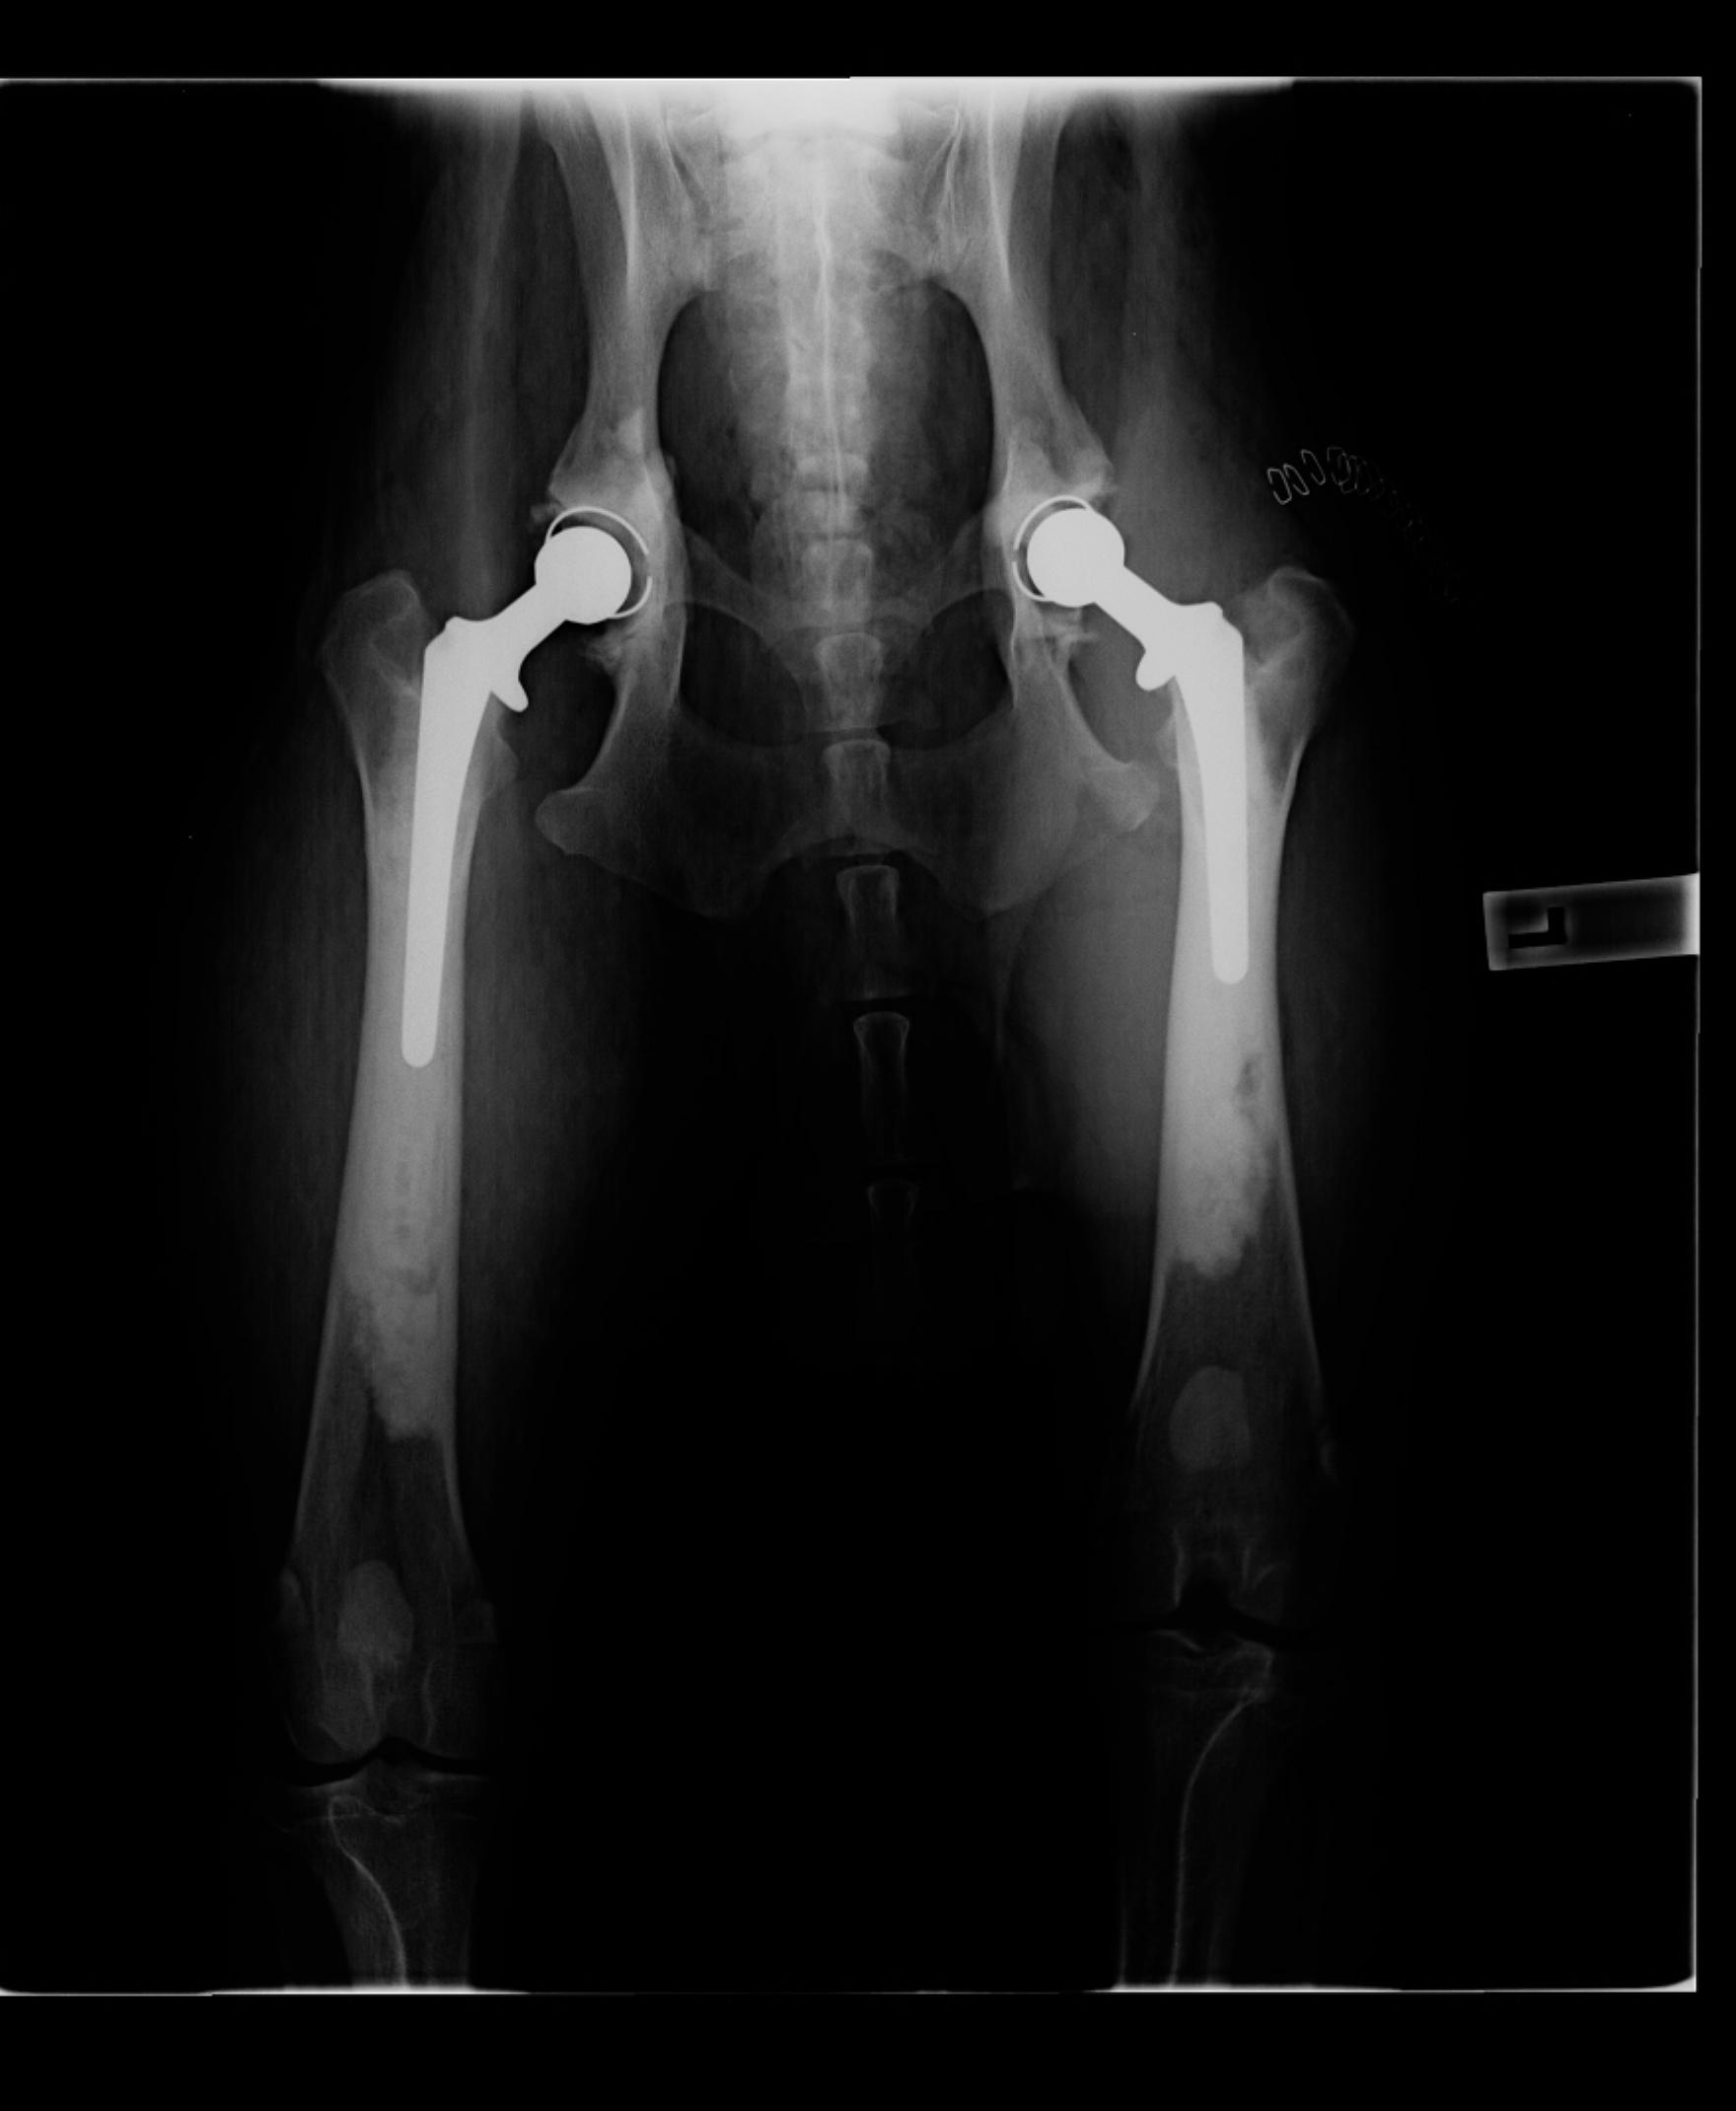

gsd_glenwood Posted June 27, 2014 Author Share Posted June 27, 2014 Hi there, I am sorry you have these worries regarding your puppy. I have a 100% working line GSD from a great breeder who does all possible health checks before her breedings. Unfortunately at 10 months of age my Cooper was diagnosed with severe HD. I had three specialists (including one who does pennhip scoring) confirm this. He had his first Total Hip Replacement done and then 5 weeks ago he had his other hip done. It is an awful shock and very expensive. I would recommend you get a specialist opinion as some vets really have no idea of correct positioning. If you have other questions, you are welcome to PM me and I will try to help. This xray is straight after his second THR I asked my vet tonight for a copy of his XRAYS - will share when I get them on a CD next week. Link to comment Share on other sites More sharing options...

Pockets Posted June 30, 2014 Share Posted June 30, 2014 Hi there, I am sorry you have these worries regarding your puppy. I have a 100% working line GSD from a great breeder who does all possible health checks before her breedings. Unfortunately at 10 months of age my Cooper was diagnosed with severe HD. I had three specialists (including one who does pennhip scoring) confirm this. He had his first Total Hip Replacement done and then 5 weeks ago he had his other hip done. It is an awful shock and very expensive. I would recommend you get a specialist opinion as some vets really have no idea of correct positioning. If you have other questions, you are welcome to PM me and I will try to help. This xray is straight after his second THR I asked my vet tonight for a copy of his XRAYS - will share when I get them on a CD next week. I would not go off the x rays your vet has taken, a GSD needs to be positioned correctly in order for someone to make an accurate assessment. Your first port of call would be to attend the vets suggested, either Karen Hedberg or Rob Zammitt, who could take x rays and give you more ideas. However as mentioned abovem German Shepherds at that age are not fully developed, so it is not possible to confirm HD/ED. German Shepherd puppies can also develop whats called "Panosteitis" which can cause limping in the front legs and generally will change from leg to leg, this will most often happen in quickly growing puppies and can be controlled by and eased by giving anti inflammortires and restricting boistrous movement during the periods that the puppy/dog is affected. I have had 2 German Shepherd male pups have this condition, its more considered to be in human terms "growth pains". Your puppy looks a bit too heavy for what I would like to see at his age, which can put unnessasary stress on growing and developing joints, they shouldnt be raised skinny, but they should not be excessively heavy either. a nice covering over the ribs and a bit of puppy fat is fine, but your pup looks like a tad bit heavy. A dog that is not positioned correctly when x rayed can look terrible, any professional x ray reader will confirm this. You have received some very good advice on here, if it were my puppy, I would be going to one of the vets recommended and discussing the concerns with them, only then will you get knowledgable answers from 2 extremely good vets that know the breed and x ray German Shepherds on a regular basis. I just had 2 of mine x rayed by Rob Zammitt and can highly recommend him. Link to comment Share on other sites More sharing options...

bianca.a Posted June 30, 2014 Share Posted June 30, 2014 To be fair though, whilst this vet may not have positioned correctly, they may be enough for a specialist to review and go from there. That is what happened with Cooper, local vet did xrays and they certainly aren't brilliant but it was clear as mud, we had a major problem. And from there we went to see specialists. Link to comment Share on other sites More sharing options...